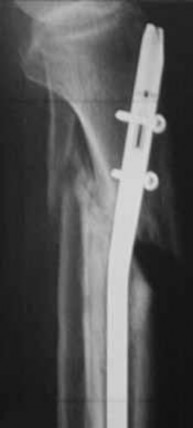

-Figures 10a and 10b are the radiographs of a 33-year-old man who was involved in a high-speed motorcycle crash. He sustained an isolated injury to the right lower extremity. On the day of injury, he was treated with open reduction and internal fixation of the femoral neck and retrograde nailing of the femur.

Radiographs are shown in Figures 10c through 10f. Alternative treatment with a cephalomedullary device alone would be more likely to lead to which of the following outcomes?